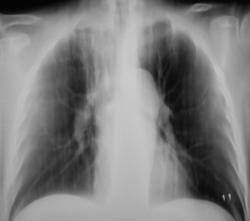

Пол пациента: Мужской пол Тип патологии: Другое Область исследования: Грудная клетка и верхние дыхательные пути Методы исследования: Rg Ранее болел туберкулёзом. Сегодня был направлен терапевтом с диагнозом пневмонии https://radiomed.ru/sites/default/files/styles/case_slider_image/public/user/12/2.dscn1413.jpg?itok=ddIwdutI https://radiomed.ru/sites/default/files/styles/case_slider_image/public/user/12/3.dscn1414.jpg?itok=BaDHOskS https://radiomed.ru/sites/default/files/styles/case_slider_image/public/user/12/4.dscn1415.jpg?itok=72LWEAHd ID:27835 Чт, 11/04/2013 - 09:53 #1 НБ Не на сайте Был на сайте: 11 лет 5 месяцев назад Зарегистрирован: 07.11.2012 - 19:55 Публикации: 84 утолщена апикальная плевра. Справа в верхней доле фиброз?. Но на ТГ не виден ВДБ, нет ли ателектаза в/доли. Н.Б. Чт, 11/04/2013 - 16:16 #2 brainmodel Не на сайте Был на сайте: 2 месяцев 2 недели назад Зарегистрирован: 18.03.2010 - 22:04 Публикации: 2881 Архив. Затем все разговоры. Verum plus uno esse non potest. Чт, 11/04/2013 - 19:26 #3 maker4ik Не на сайте Был на сайте: 8 лет 7 месяцев назад Зарегистрирован: 19.10.2011 - 17:49 Публикации: 2682 Не увидела пневмонию. И свежих очагов тоже. Чт, 11/04/2013 - 19:55 #4 Сергей Кузьминов Не на сайте Был на сайте: 1 год 2 недели назад Зарегистрирован: 06.10.2012 - 15:51 Публикации: 11813 Активного лёгочного процесса нет.Посттуберкулёзные изменения есть.

утолщена апикальная плевра. Справа в верхней доле фиброз?. Но на ТГ не виден ВДБ, нет ли ателектаза в/доли.

Не увидела пневмонию. И свежих очагов тоже.

Активного лёгочного процесса нет.Посттуберкулёзные изменения есть.